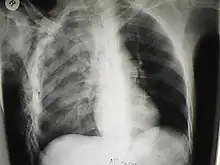

| A chest X-ray of a right sided pulmonary contusion associated with flail chest and subcutaneous emphysema | |